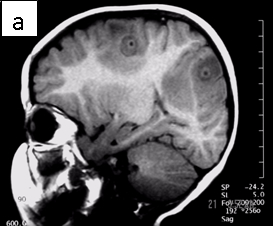

Figure 1: Neurocysticercosis in an 18-month child. a. Sagittal T1 without gadolinium; b. Axial T1 with gadolinium; c. Axial T2; d. Coronal FLAIR

Radiologic diagnosis: Neurocysticercosis.

| CT scan | A variable appearance including multiple, low-density lesions, 0.5 to 2.0cm in diameter. In acute disease, they enhance after contrast administration, surrounded by vasogenic edema with or without mass effects. Dead parasites (not dying parasites) show as non-enhancing calcified 5mm bodies. |

| MRI | Live forms have a characteristic appearance: fluid-filled lesions containing an inverted scoleces, surrounded by thin low-signal capsule. They do not stimulate inflammation and do not enhance; dying forms do. In the less common racemose type, the cysts may be hard to see because they have similar imaging features as the CSF. |